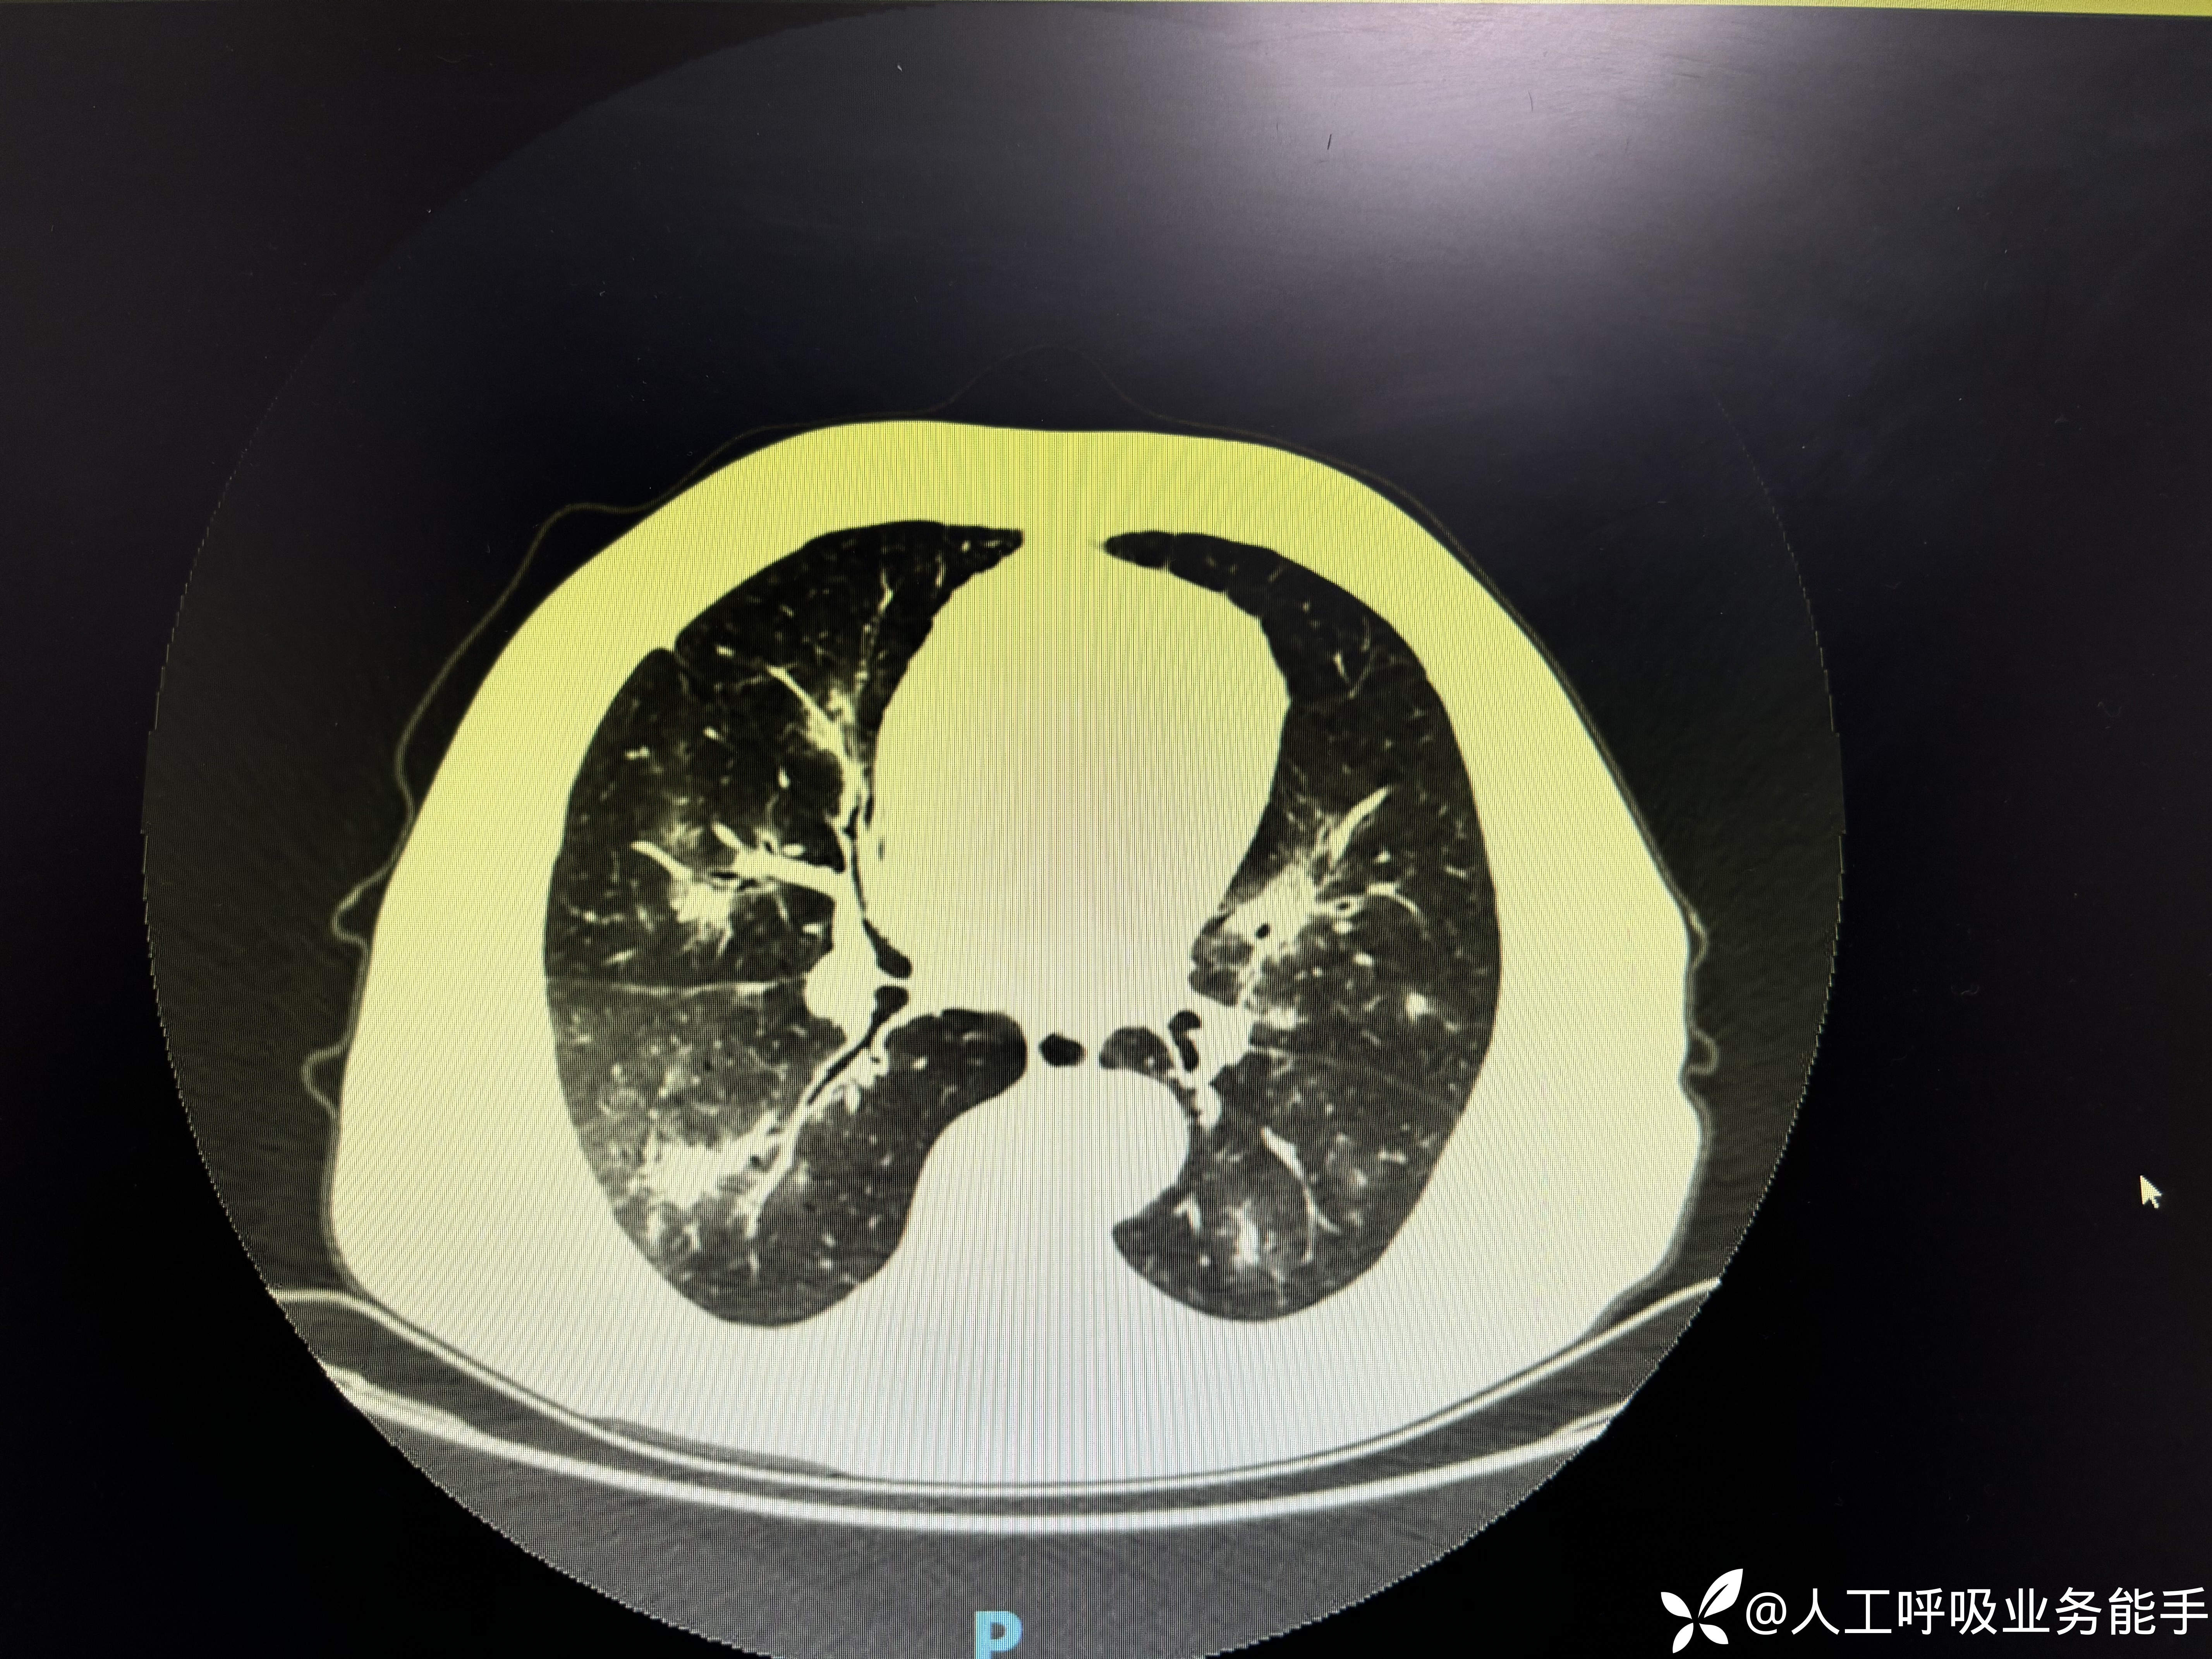

-1/26到我院急诊内科,血常规:WBC 10.71*109/L,CRP 111.6mg/L,Hb 128g/L,PLT 213*109/L,N 68% L 10% Eos 15%;尿常规:黄色清亮,蛋白质 1+,红细胞 2+,白细胞 -,复查胸部CT:

-胸部CT提示双肺多发病变,较前明显进展;